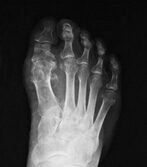

(图:治疗前鲁先生的x光图,可明显看出拇指关节肿大、外翻)

X线示:左足跖骨骨头处出现溶骨性缺损。